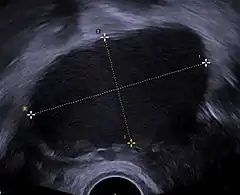

![]() Ecografía ginecológica en la que es visible un endometrioma ovárico de 67 x 40 mm. | ||

El 50% de las mujeres afectadas de endometriosis desarrollan endometriomas a lo largo de su vida que generalmente son bilaterales, es decir afectan tanto al ovario derecho como al izquierdo. El diagnóstico puede sospecharse por los síntomas y una ecografía abdominal, pero para obtener un diagnóstico definitivo es preciso el estudio del tejido mediante técnicas de anatomía patológica. En aquellas mujeres diagnosticadas previamente de endometriosis, la existencia de una masa quística en ovario es muy sugestiva de endometrioma.[1]